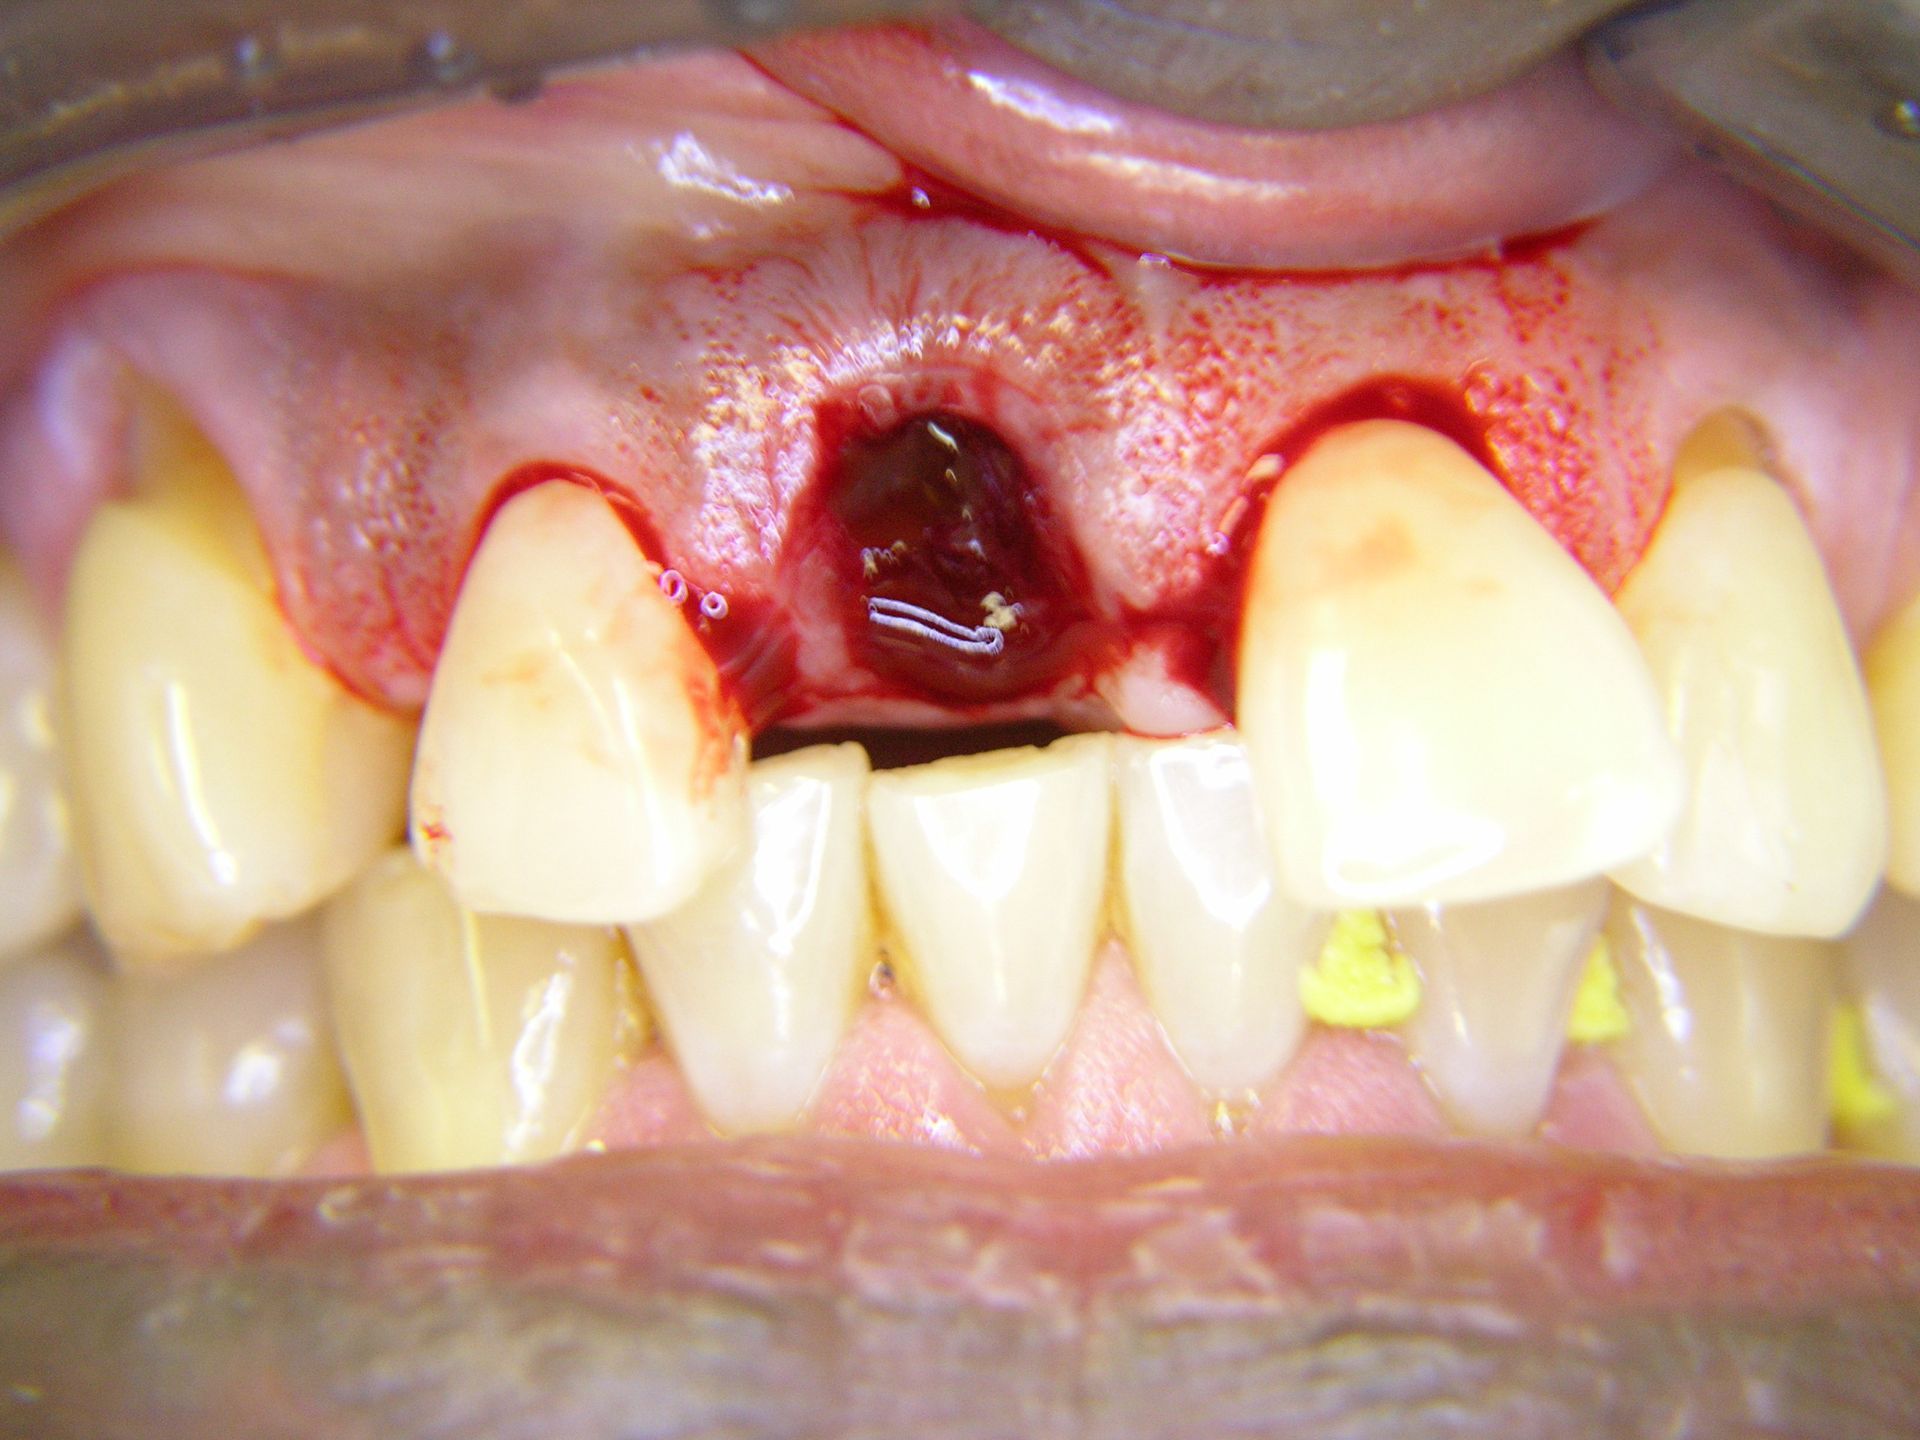

Beispiele von Versorgungen